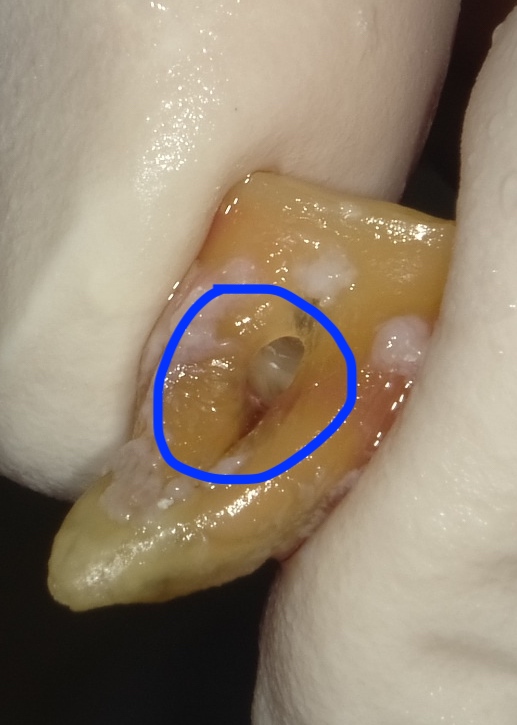

画像の様なイメージになります。針金を使いませんので

見た目がよくまた維持力も大きくとても良好な義歯となります。